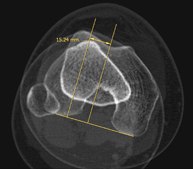

- Lower leg rotational study using CT [patella, tibial tuberosity to trochlear groove (TT-TG) distance]

Radiological examination based on an X-ray system and detectors that rotate around the patient, reconstructing the images by computer (multidetector computed tomography - MDCT) to calculate a series of measurements at the hips, knees and ankles with a view to solving problems affecting the rotation and angulation of the lower limbs.